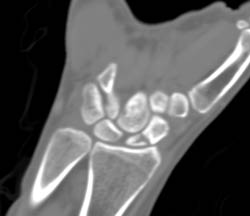

Scaphoid Fracture